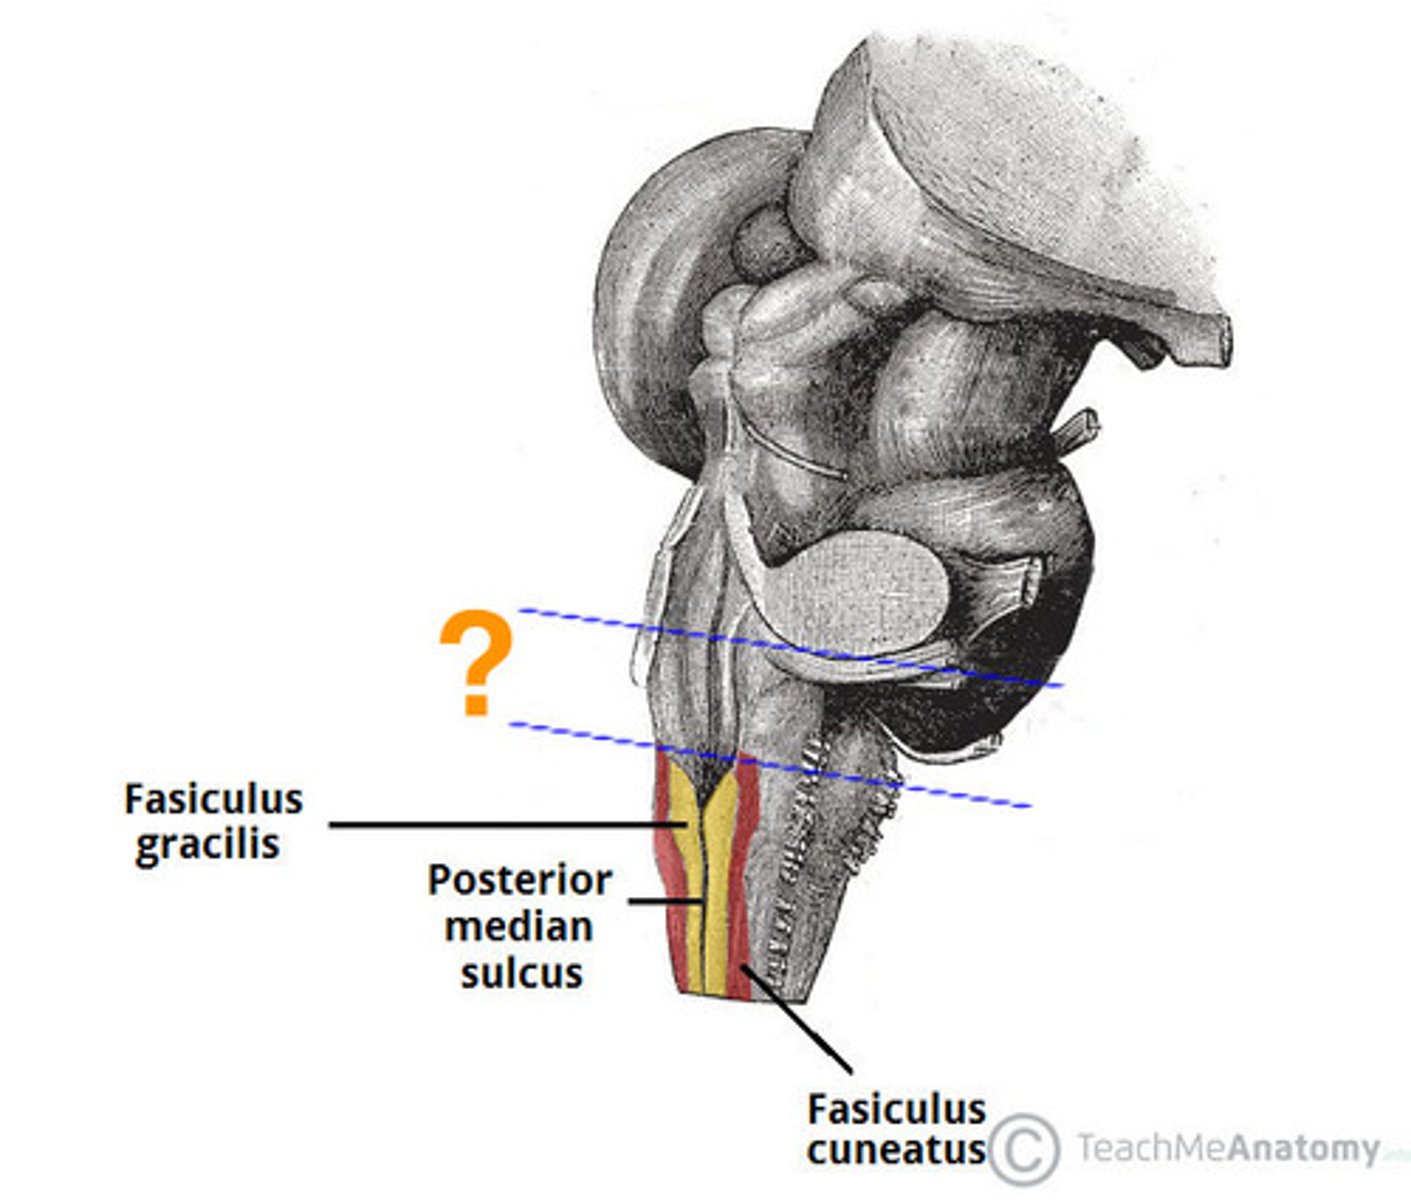

medial paired ridges of tissue on the dorsal aspect of the closed portion of the medulla

tractus gracilis

lateral paired ridges of tissue on the dorsal aspect of the closed portion of the medulla

tractus cuneatus

superior ends of the medial paired ridges of tissue on the dorsal aspect of the closed portion of the medulla, formed by namesake nuclei

gracilis tubercles

superior ends of the lateral paired ridges of tissue on the dorsal aspect of the closed portion of the medulla, formed by namesake nuclei

cuneatus tubercles

name the groove

pontomedullary junction

general portion of the medulla

open medulla

general portion of the medulla

closed medulla

pyramids

ventral median fissure

pyramidal decussation

C

inferior cerebellar peduncles

cuneate tubercle

gracilis tubercle

cuneatus tract

gracilis tract

obex